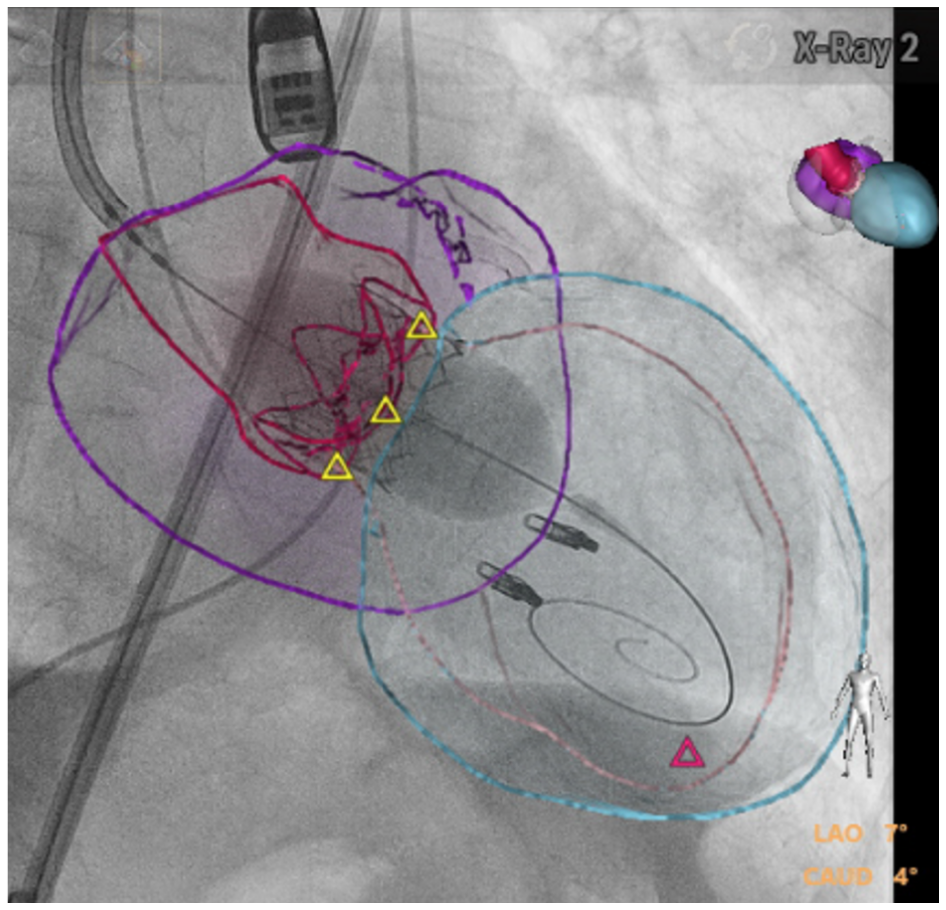

Procedural details of TAVI for AR. TAVI was performed in a hybrid operation room under general anesthesia and using intraprocedural transesophageal echocardiography fusion imaging technique (Figure 1). The technique allows the overlaying of 2D- and 3D-echocardiography on fluoroscopy and provides an ECG-gated 3D model of the heart as well. The model of the aortic valve is merged and superimposed on the fluoroscopic images, helping in defining the optimal fluoroscopic projection for the implantation as well as for the precise placement of the aortic prosthesis at the level of the annulus.10 In the absence of valve calcification (typically used as an anatomical landmark during TAVI in aortic valve stenosis), the model facilitates the correct positioning of the valve prosthesis within the annulus. The implantation itself does not differ much from the usual TAVI procedure for aortic stenosis, while the landing zone is typically high. In all patients, an Edwards SAPIEN-3 THV (Edwards LifeSciences) was used with at least 10% oversizing based on CT measurements to ensure adequate annular fixation. All procedures were performed under general anesthesia with periprocedural transesophageal echocardiography. Arterial access via the femoral artery using fluoroscopic-guided puncture and Seldinger technique was used for all cases. Rapid pacing was applied in all patients for stable and precise valve release. This was done over the left ventricular guidewire (Safari2, Boston Scientific) in all patients in order to additionally prevent the implantation of a transvenous temporary pacemaker and its possible associated complications.

The currently available THVs are designed for the treatment of calcified stenosis, relying on the fixation within an extensively calcified aortic valve annulus and cusps. In contrast in native AR, where disease often extends to structures other than the aortic valve alone and often calcification is rare, TAVI is not a common procedure. Presently, the only THV with CE approval for pure AR is the JenaValve. Overall, most TAVI cases of pure AR performed used self-expandable THVs. We are reporting our single center experience in consecutive patients with severe AR in native non or mildly-calcified valves treated with balloon-expandable Edwards Sapien-3 prosthesis. This is, to our knowledge, the largest case-series of patients with non or mildly calcified AR treated with the Edwards Sapien-3 valve. Upon adequate patient selection and consideration of the anatomical aspects of the annulus, good clinical outcome can be achieved. Even though implantation can be technically difficult due to missing anatomical landmarks, TAVI for pure AR is feasible with favorable clinical outcome in high-risk patients deemed inoperable. The use of fusion echocardiographic imaging technique, allowing the overlaying of 2D and 3D echocardiography on fluoroscopy in real time and providing an ECG-gated 3D model of the aortic valve may potentially help in defining the optimal position for device implantation in absence of calcium. This is reflected in the relative small amount of contrast agent used in this collective of patients. In our limited series, successful implantation was achieved in all patients with no device embolization or migration. Complications appear not to differ from the ones typically seen in percutaneous treatment of severe AS using the same device and includes vascular access complication as well as the need of pacemaker implantation due to high-degree AV block.